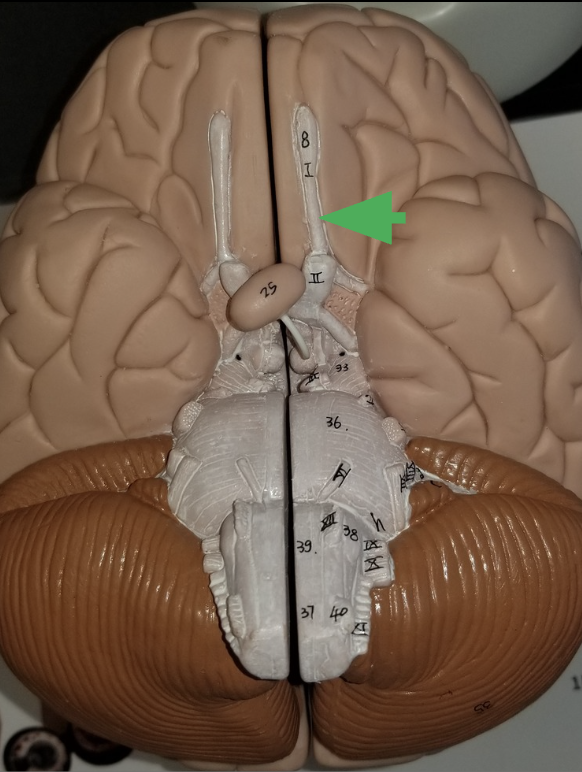

What is the arrow indicating?

1 of the 2 cerebral hemispheres

what does the arrow indicate?

Olfactory bulb

What is the function of an olfactory bulb?

Receives input from olfactory neurons coming from nasal cavity

Olfactory Track

What does the olfactory tract do?

carries information from the olfactory to the cerebrum, where it can be sorted, interpreted, and processes

Optic Nerve (cranial nerve 2)

What does the optic nerve do?

carries axons from retina of the eye

what does the arrow indicate ?

Optic chiasm

What happens in the optic chiasm?

where some axons in each optic nerve cross over to the other side

What does the arrow indicate?

Optic Track

What does the optic track do?

carry axons from optic nerves ro the thalamus

What is the arrow pointing at?

Oculomotor nerve

What is the arrow indicating?

Trigeminal nerve (cranial nerve 5 /V )

What does the trigeminal nerve do?

Carries sensory information from the face

Carries motor commands to chewing muscles